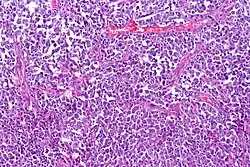

Lymphoma cancer types have varying probabilities of metastasizing to the CNS, resulting in secondary CNS lymphoma (SCNSL), which may appear simultaneously as systemic lymphoma, or as remission after systemic lymphoma is treated. Synchronous, or de novo disease is diagnosed in approximately 40% of patients and relapse in 60%.[8] Overall, CNS involvement is observed in 2 to 27% of patients with aggressive systemic non-Hodgkin’s lymphoma.[5] 5% of patients with diffuse large B cell lymphoma, the most common type of non-Hodgkin lymphoma, result in SCNSL but account for most SCNSL cases.[3]